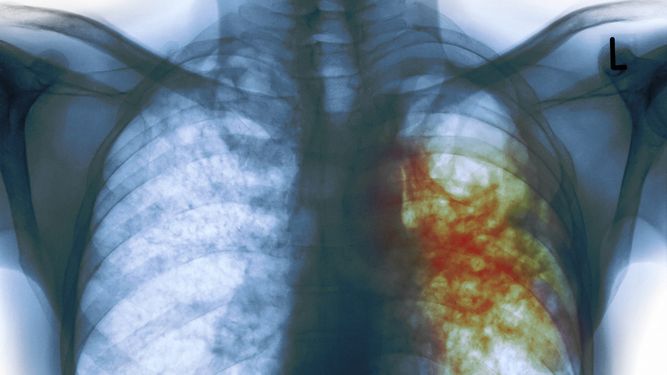

Se estima que el 20 por ciento de las personas con diabetes muestran una fibrosis hepática "muy importante, con alto riesgo de desarrollar cirrosis", según la división de Endocrinología, Diabetes y Metabolismo de la Universidad de Florida, EEUU Kenneth Cusi